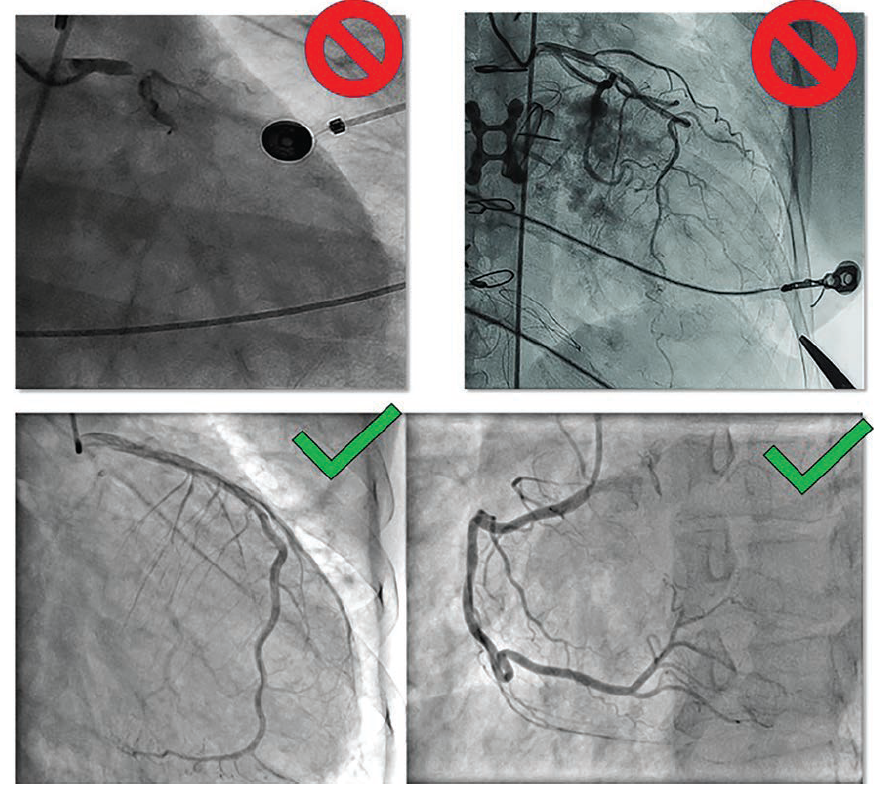

Artifacts in radiographic medical imaging are any unwanted elements or conditions that obscure the clarity of the images. Foreign objects in the image field can compromise the quality of the cardiac structures and may overlap with coronary vessels, making for an inaccurate interpretation. In the cath lab, some of these artifacts include wires or patches from electrocardiogram (EKG) leads, metal objects from gowns, underwear or jewelry (or metal prostheses), oxygen tubing, CO2 cables, and defibrillator pads (Figures 1-4). Some imaging artifacts were out of our control; that is, they were due to problems related to the operator’s technique of coronary arteriography and the activities performed by the physician operators. Proper angiographic techniques are designed to reduce or eliminate artifacts due to contrast streaming, vessel or branch overlap, image foreshortening, poor contrast injection, or any x-ray function (eg, underexposure or overexposure), any or all of which can reduces adequate image opacification. There are patient-related artifacts from implanted devices, like pacemakers, loop recorders, implantable cardioverter defibrillators (ICDs), coronary artery bypass graft (CABG) sternal wires, or orthopedic metal joints that may obscure or degrade image quality. Again, any physician-directed or patient-related artifacts, such as positioning, angiographic setup, and contrast injections were not part of this quality improvement project.

We developed a series of visual aids and sample materials to clearly demonstrate the types of artifacts and their impact on imaging quality.

Step 2: Implementing Staff Training. Educational material, in the form of a PowerPoint presentation (example shown as part of Figure 5), was delivered to every staff member involved in the cath lab and imaging process. The training sessions emphasized the importance of removing potential artifacts before imaging and provided practical tips on how to do so effectively.